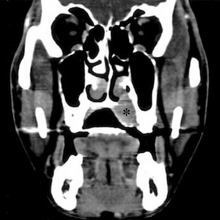

| Top: Ewing sarcoma of the thigh bone on a child's CT scan Bottom: Extraskeletal Ewing sarcoma of the hard palate | |

MRI will show the full bony and soft tissue extent and relate the tumor to other nearby anatomic structures (e.g. vessels). Gadolinium contrast is not necessary as it does not give additional information over noncontrast studies, though some current researchers argue that dynamic, contrast-enhanced MRI may help determine the amount of necrosis within the tumor, thus help in determining response to treatment prior to surgery. Computed axial tomography (CT) can also be used to define the extraosseous extent of the tumor, especially in the skull, spine, ribs, and pelvis. Both CT and MRI can be used to follow response to radiation and/or chemotherapy. Bone scintigraphy can also be used to follow tumor response to therapy. In the group of malignant small round cell tumors that includes Ewing sarcoma, bone lymphoma, and small cell osteosarcoma, the cortex may appear almost normal radiographically, while permeative growth occurs throughout the Haversian channels. These tumors may be accompanied by a large soft-tissue mass while almost no bone destruction is visible. The radiographs frequently do not shown any signs of cortical destruction. Radiographically, Ewing's sarcoma presents as "moth-eaten" destructive radiolucencies of the medulla and erosion of the cortex with expansion.[citation needed]

CT scan face- extraskeletal Ewing sarcoma hard palate